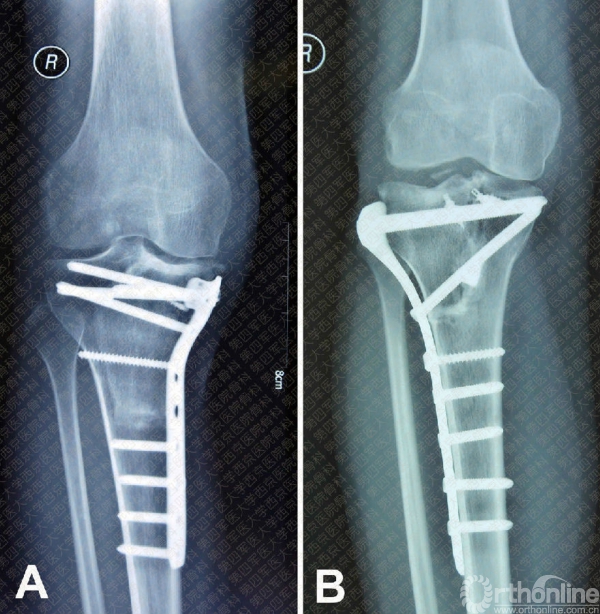

The average operation time was 216 minutes(ranging from 85 to 300 minutes) and average blood loss during surgery was 678ml (ranging from 150 ml to 3000 ml). There was no neurovascular bundle injuryoccurred during surgery. The follow-up time ranged from 17 to 43 months (median:27.5 months). Two patients with OS were found to have pulmonary metastasis at 5and 10 months postoperatively. After interventional radiotherapy for metastaticlesion, they were now alive with disease (AWD). No local recurrence or metastasiswas observed in rest patients. At the time of their last follow-up, 12 patientswere alive without evidence of disease (AWED). They had an average functionalscore of 25.7±1.1 points. X-ray film of follow-up showed the good bone healing.There was no joint narrowing, subchondral bone collapse, limb lengthdiscrepancy, and screw loosening in any of the patients (Fig.8A). In contrast, X-ray filmof implantation with manually selected allograft showed the delayed bonehealing and joint degeneration in one patient before establishment of 3-Dvisual bone bank system (Fig.8B).

Figure8: (A) X-ray filmshowed the reconstruction with 3-D visual bone bank selected allograft inpatient with right proximal tibial osteosarcoma at 22 months postoperatively;(B) X-ray film showed the reconstruction with manually selected allograft inpatient with right proximal tibial giant cell tumor at 24 monthspostoperatively.